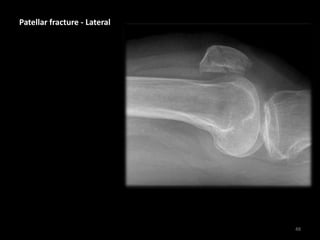

Patellar fracture - Lateral

• Increased density

separating the fat

pads indicates a

joint effusion due to

leakage of blood

(haemarthrosis)

49